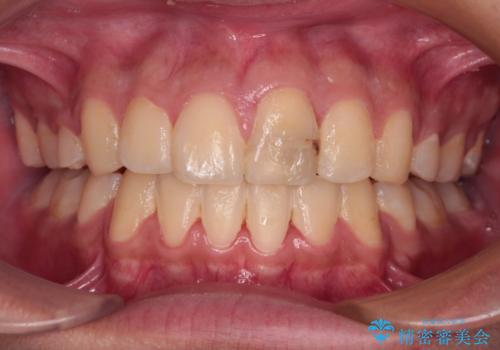

膨らんだ口元 ワイヤー装置での抜歯矯正

- 口元の突出感を気にして来院された患者様です。

上下前歯が著しく前突している状態であったので、上下左右の第1小臼歯4本を抜歯し、ワイヤー装置にて矯正治療を行うこととしました。

小学生の頃に上顎前歯をぶつけ、歯の一部が破損している状態であったので、歯根が歯槽骨と癒着して移動しない可能性がありましたが、無事に治療を終えることができました。